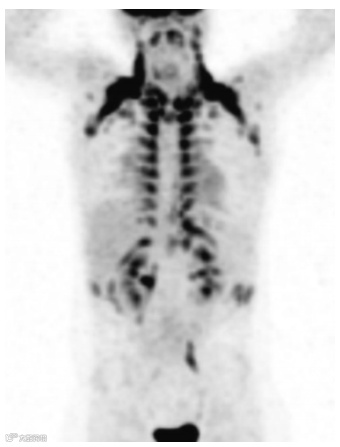

在颈部、锁骨上区、腋窝、纵隔、椎旁和肾周区域的活化棕色脂肪组织分布中可以观察到生理性高摄取(图15)。FDG(一种葡萄糖类似物)的摄取,当棕色脂肪组织中的葡萄糖转运蛋白被激活时就会发生。自从PET引入以来,人们已经知道激活的棕色脂肪组织中生理性的FDG摄取是假阳性结果的一个来源。棕色脂肪中的FDG摄取通常是双侧和对称的。然而,局部和不对称的摄取可能发生在颈部或纵隔,导致假阳性结果。FDG PET/CT 联合显像提供了精确的解剖相关性,可以区分CT上脂肪衰减组织对应的FDG摄取和病理原因引起的摄取。儿童棕色脂肪中的摄取比成人更常见,并且在冬季最常见。在注射前和摄取阶段对患者进行保暖是一种简单的方法,有很多机构常规使用此方法减少棕色脂肪的摄取。注射前使用地西泮、芬太尼或普萘洛尔也可避免棕色脂肪FDG的摄取。

图15. MIP FDG PET 图像显示儿童患者棕色脂肪组织摄取的典型分布。摄取位于颈部、锁骨上和腋窝区域、纵隔、椎旁和肾周区域以及腹前壁。